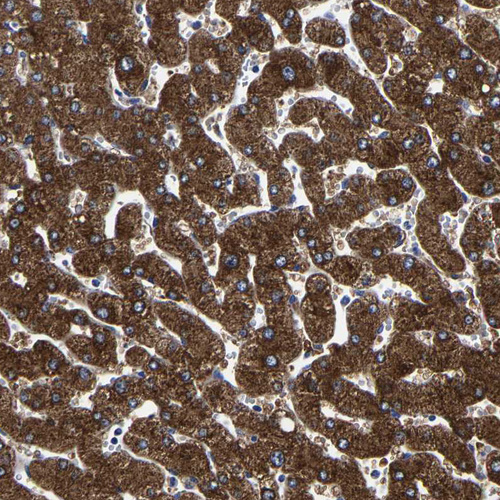

Immunohistochemistry analysis in human liver and skeletal muscle tissues using HPA020734 antibody. Corresponding AASS RNA-seq data are presented for the same tissues.